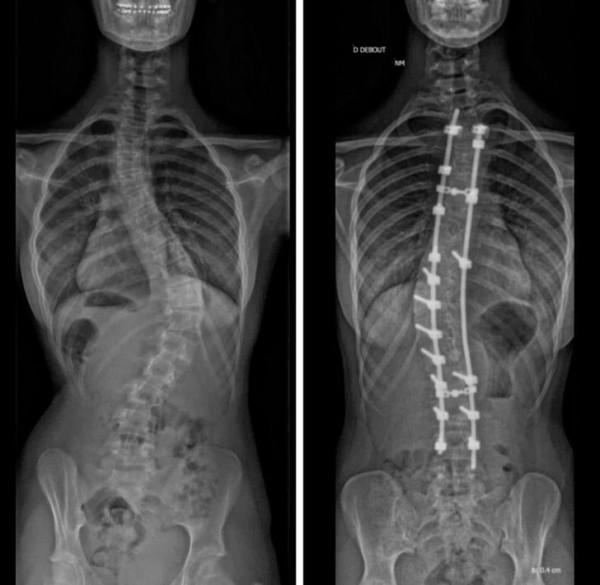

脊柱矯正手術之前/之後的結果